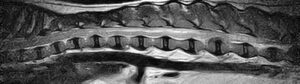

フレブルちゃん両後肢麻痺グレード5でMRI検査及び手術依頼でご紹介がありました。MRI検査で第4-5腰椎間椎間椎間板ヘルニア、右側優位な圧迫と診断し即日手術となりました。→<その2>へ続く